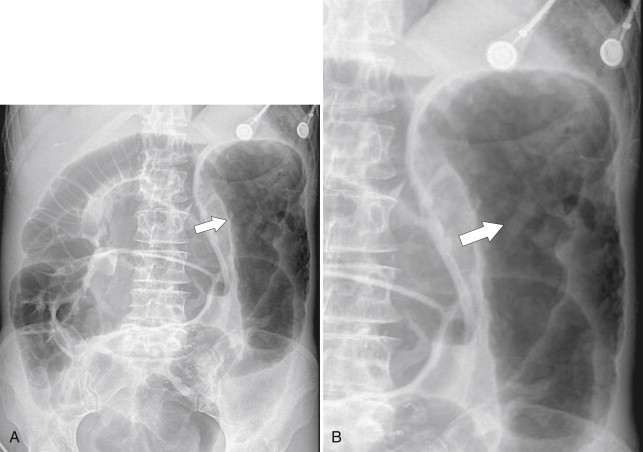

Plain radiography may demonstrate an ileus, sometimes confined to the left colon. As the disease progresses, bowel wall thickening develops ( Fig. 5-34 ) with a toxic megacolon if severe ( Fig. 5-35 ). BE is now rarely performed, but results demonstrate thickened folds and ulceration, either linear or with mucosal sloughing. Healing can lead to stricture formation ( Fig. 5-36 ). The findings are now usually made by CT and are similar to other forms of colitis (inflammatory bowel disease, infectious colitides, and radiation colitis if the radiation field included the colon). The disease is suggested in the appropriate clinical setting and by the left-sided distribution of the colonic changes ( Fig. 5-37 ). Severely affected patients show colonic pneumatosis as the gas permeates the damaged mucosa, which can then enter the mesenteric venous system and be recognized as mesenteric venous gas (particularly at CT) and ultimately intrahepatic portal venous gas. Occasionally, ischemia occurs proximal to an obstructing colonic stricture, such as colonic adenocarcinoma. The obstruction causes marked distention of the proximal colon, compromising its vascular supply or directly invading mesenteric vasculature ( Fig. 5-38 ).

Figure 5-35, A and B, Plain abdominal radiograph ( A ) and magnified view ( B ) in a 56-year-old man with a left-sided toxic megacolon due to ischemic colitis. There is thumb-printing of the colonic mucosa at the splenic flexure ( arrows ).